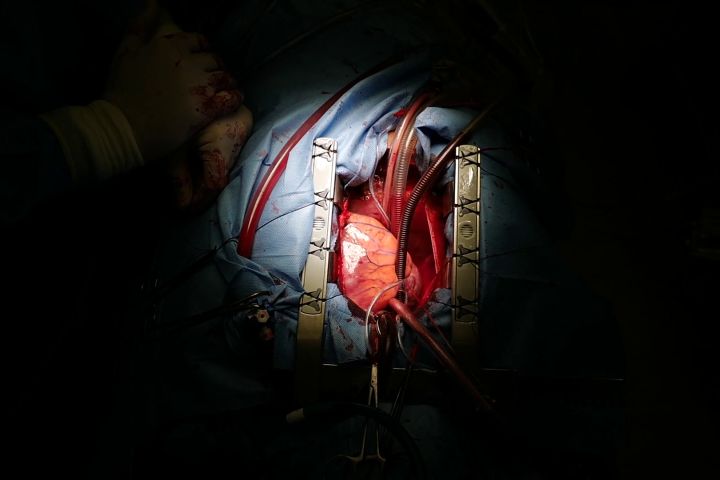

Srdce pacienta pred vyňatím Zdroj: NÚSCH

Srdce pacienta pred vyňatím Zdroj: NÚSCH